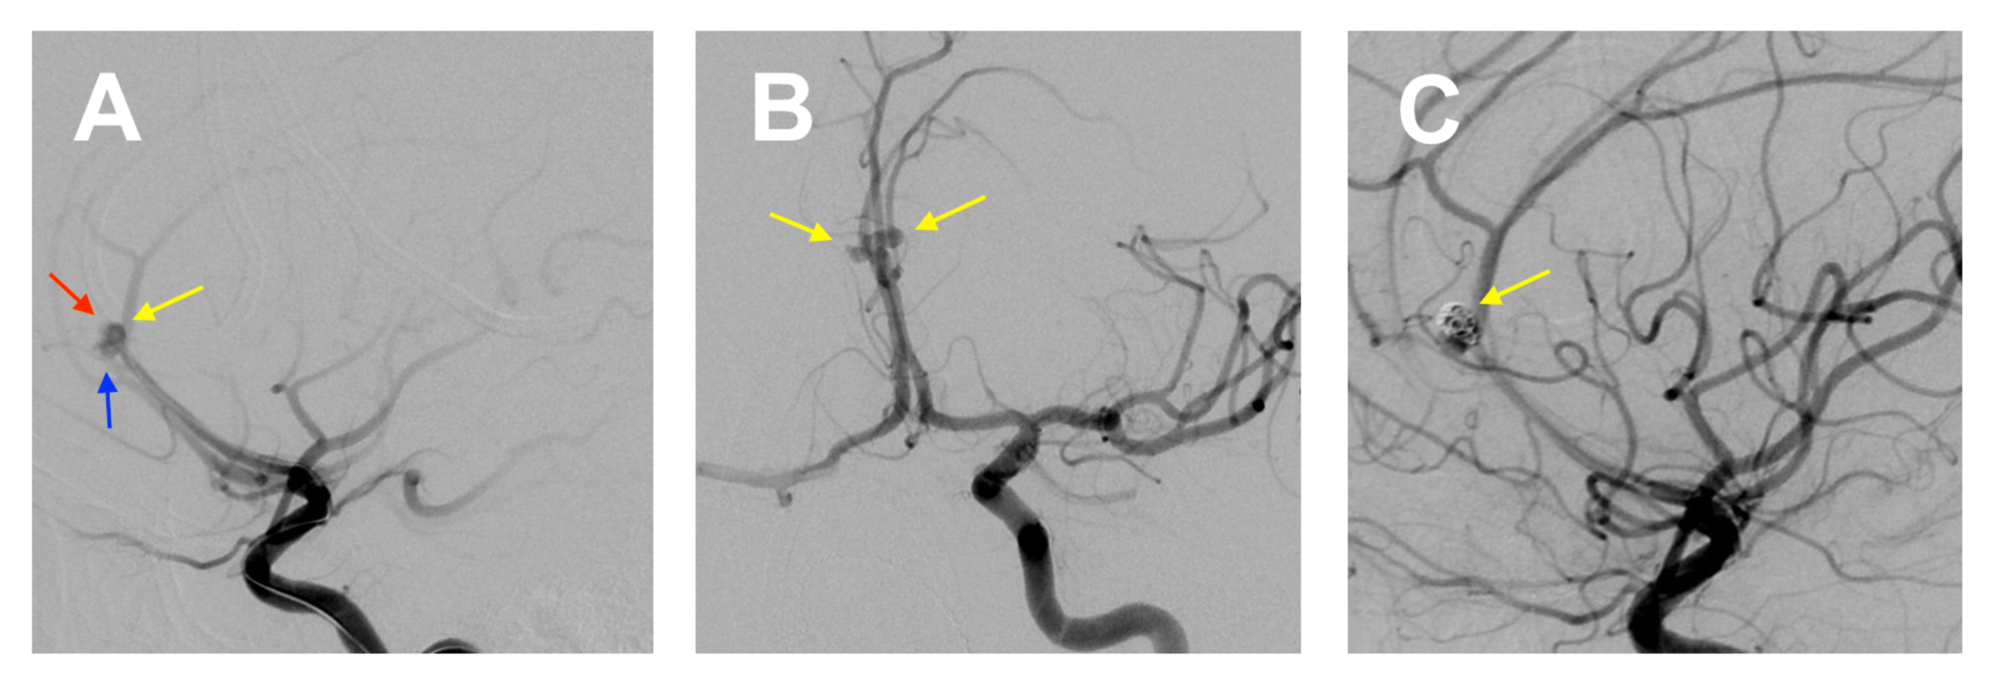

A coil can stop a ruptured aneurysm from continuing to bleed or prevent an unruptured. Image of ICA aneurysm prior to stent-assisted coiling Post-Surgery Care After surgery a. Learn About the Causes Symptoms and Treatment Options for an Aortic Aneurysm.